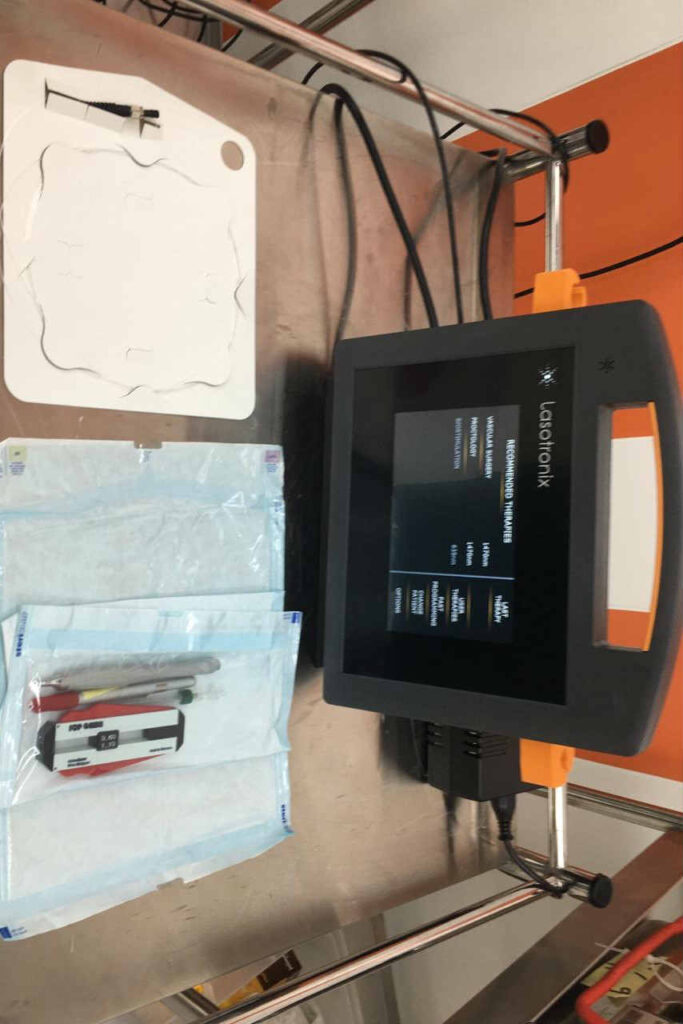

جهاز الليزر لعلاج البواسير والناسور الشرجي والناصور العصعصي